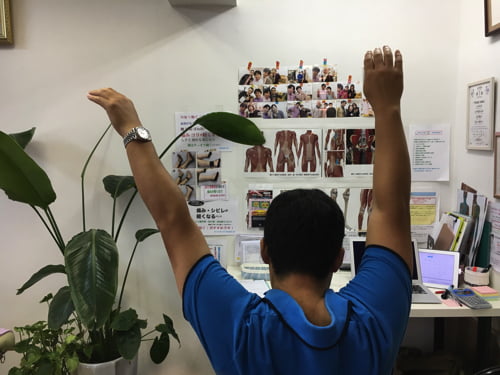

痛みの出る場所はこの辺りです。

この動作の際には、後ろ側に痛みが出ます。